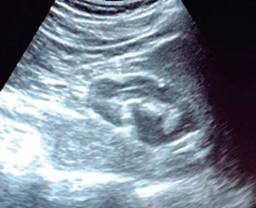

El cirujano general aborda particularmente problemas clínicos que incluyen el aparato digestivo, el cuello, la pared abdominal y los trastornos del sistema circulatorio y el tórax. Un artículo publicado en 2008, por Lindelius,15 demostró que la implementación del ultrasonido por parte del cirujano general en casos de dolor abdominal agudo incrementó en 7.9% la precisión diagnóstica. En la consulta cotidiana de la especialidad, incorporar el rastreo sonográfico al área explorada agrega minutos al examen clínico que aportan datos de notable valor por la objetividad y precisión. El abdomen suele ser el sitio que los cirujanos generales exploramos con más frecuencia. Es posible en una consulta cotidiana hacer todo el protocolo de ultrasonido de abdomen superior en minutos, que incluye ambos cuadrantes superiores y los flancos, pudiendo observar el hígado, la vesícula y los conductos biliares, ambos riñones, el bazo, parte del páncreas y, con ayuda del Doppler color, los principales vasos de la región como la vena cava inferior, la aorta abdominal, la vena porta, los vasos esplénicos y la arteria hepática. Puede haber limitantes como el contenido gástrico, el nivel de llenado de la vesícula biliar o la constitución del paciente y su capacidad de cooperar con el estudio. Pero con la práctica cotidiana, se adquieren las destrezas y el refinamiento suficientes para lograr, con la experiencia acumulada, producir imágenes de relevancia diagnostica inmediata. En la fase de entrenamiento, contrastar nuestros hallazgos con información disponible en la red, con los colegas imagenólogos, o cirujanos ya experimentados en ecografía, permitirá la retroalimentación y la tutoría esenciales de toda curva de aprendizaje. Tradicionalmente se consideraba que aquellos órganos que contienen una mezcla de líquido y gas (intestino, estómago) no son valorables por ultrasonido, el gas produce un efecto rarefacción, ya que no comprime las ondas como un tejido solido o un medio líquido, la señales entonces se dispersan impidiendo que regresen como ecos y permitan al procesador formar una imagen congruente con el órgano explorado. Sin embargo, cuando esta condición cambia como consecuencia de un estado patológico, es posible identificar el contenido intestinal o el gástrico y darnos una idea más aproximada de lo que realmente está ocurriendo en ese abdomen. Podemos, por ejemplo, saber si un estómago está lleno de líquido, o si el intestino contiene residuo sólido, líquido o gaseoso. Los equipos actuales pueden incluso ver en detalle la pared intestinal cuando ésta esté dilatada. Se puede distinguir cuando el colon está ocupado de líquido a nivel del flanco izquierdo como podría ser en una colitis amebiana o en una oclusión intestinal,16 donde se observa dilatación del intestino delgado ≥ 25 mm, el peristaltismo anormal, la presencia de líquido libre intraperitoneal y el edema de la pared intestinal (Figura 2). En casos de dolor abdominal agudo, el ultrasonido puede, en forma inmediata, permitir diagnósticos diferenciales como el hallazgo de una dilatación pielocalicial por nefrolitiasis (Figura 3), o un aneurisma de la aorta abdominal (Figura 4). Un estudio prospectivo realizado en Irvine, California,17 encontró que la a capacidad diagnóstica del médico de primer contacto practicando el ultrasonido para detectar una colelitiasis tiene una especificidad de 87% y una sensibilidad de 82%, mientras que la prueba de ultrasonografía realizada por radiología tuvo sensibilidad de 83% y una especificidad de 86%. Es decir, que, ahorrando tiempo al paciente, el diagnóstico de colelitiasis es factible agregando unos minutos al examen físico inicial. En casos de apendicitis, el método diagnostico considerado como el estándar de oro es la tomografía axial computarizada (TAC). Sin embargo, tiene inconvenientes como su disponibilidad, su costo, el riesgo de radiación en niños y pacientes embarazadas. En tales situaciones, sobre todo en niños, sexo femenino o pacientes delgados, el ultrasonido es una poderosa herramienta que complementa el examen clínico inicial. Las ventajas del ultrasonido frente a la tomografía serian su ubicuidad (ya está en la sala de emergencias), el bajo costo, la ausencia de radiación y el diagnóstico diferencial con causas ginecológicas o genitourinarias de dolor. En apendicitis, la sensibilidad y especificidad de la TAC es de 99.4% y 80.0%, respectivamente. Para el ultrasonido, la sensibilidad diagnóstica es de 83% y la especificidad de 90%. La tasa de apendicectomía negativa es ligeramente mayor en el grupo de TAC que en el del ultrasonido, es decir, 7.1% (3/42) (TAC) en comparación con 4.67% (5/107) (ultrasonido). Hay que recalcar que el ultrasonido es operador dependiente. La experiencia y la calidad del equipo juegan un papel importante.18 La apendicitis tiene varios hallazgos característicos, como la pared edematosa y el aumento de grosor general. Se toman para criterios de positividad una estructura tubular aperistáltica no compresible que mide más de 6 mm de diámetro en el cuadrante inferior derecho (Figura 5).19-21

Figura 3: Dilatación pielocalicial izquierda en un paciente que acude a consulta por dolor abdominal agudo.